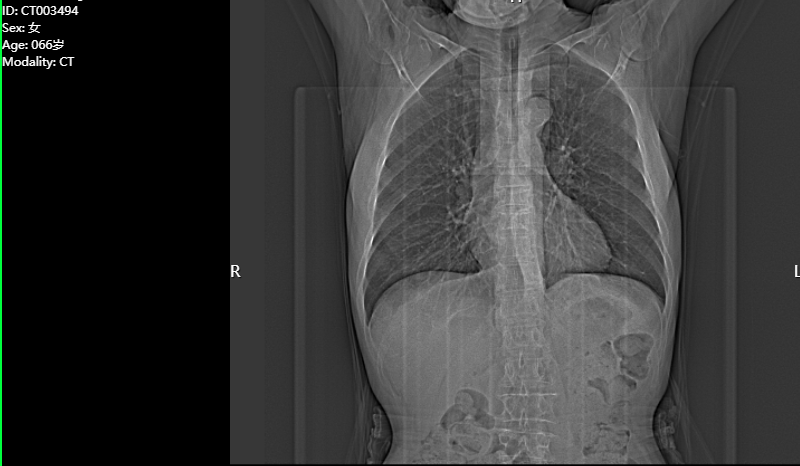

放射診斷報(bào)告工作站:放射診斷醫(yī)生工作站支持不同類型(如CT、MR、CR、DR、XRA、DSA)的影像設(shè)備所采集圖像的閱讀、后處理、書寫診斷報(bào)告等。